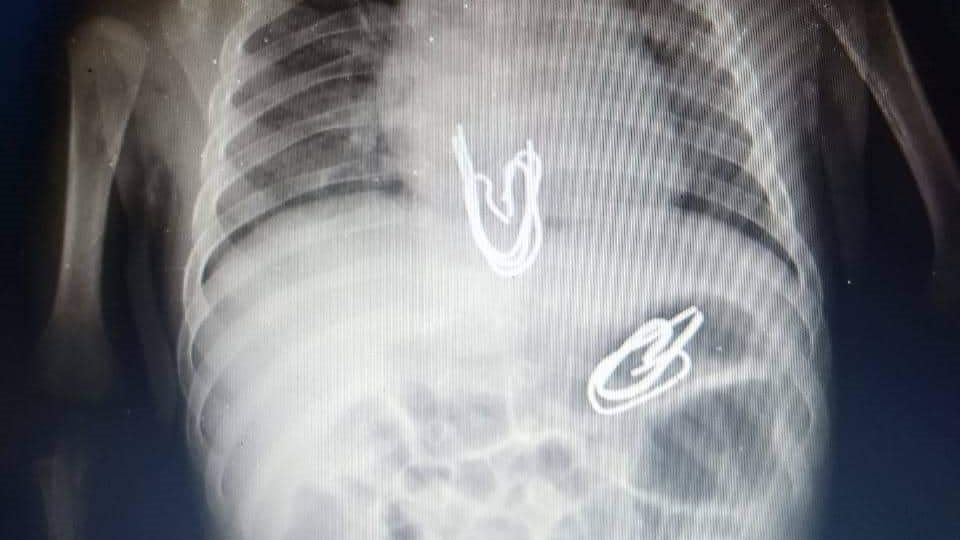

وأفادت الأم بأنها تركت طفلها الرضيع لفترة وجيزة مع أخته التي تبلغ من العمر ثلاثة سنوات التي قالت أنها وضعت دبابيس معدنية، تستخدم في تعليق الستائر في فم الطفل وبعد عمل أشعة علي البطن تبين وجود مجموعة من الدبابيس في المرئ وأخرى في المعدة.

وا ضح الفريق الطبي أن هذه الدبابيس ذات أطراف حادة وكان هناك تخوف من أن تكون جرحت جدار المعدة والمرئ، وتم عمل أشعة مقطعية أثبتت عدم وجود جروح في جدار المعدة والمرئ.